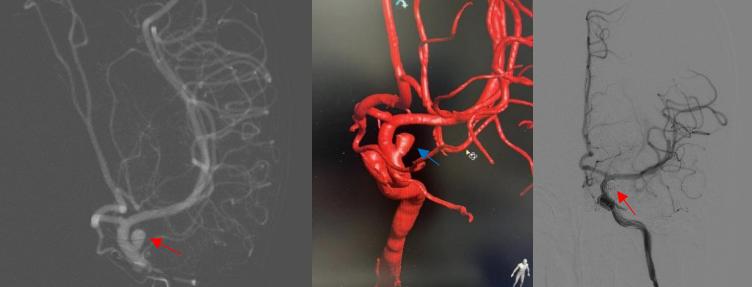

进行MRA检查后,提示左侧大脑中动脉接近闭塞。大脑中动脉是脑内很重要的血管,一旦发生血管闭塞,会出现肢体瘫痪、失语等表现,严重时会导致昏迷,抢救不及时甚至会危及生命。患者及家属对此很是担心,因为作为家里的顶梁柱一旦瘫痪倒下,整个家庭将陷入巨大的危机。别小华主任向他们讲述了病情及治疗方案,告知可以通过血管介入手术治疗。患者家属怀着忐忑的心情办理了入院手续

术前检查完成后,神经外科介入团队于6月14日在局麻下给患者行全脑血管造影检查提示“颅内多发动脉粥样硬化伴狭窄,左侧大脑中动脉M1段重度狭窄”。左侧大脑中动脉仅余一线,狭窄率接近99%。考虑患者反复出现脑梗死与左侧大脑中动脉狭窄有关。且其它血管对左侧大脑中动脉供血区域基本无代偿,一旦发生大脑中动脉闭塞将发生严重后果,有明确的手术指征。与患者及家属沟通病情后决定行颅内动脉狭窄血管内介入治疗。后改为气管插管全身麻醉,术中严格控制血压。因患者血管迂曲,神经外科介入团队使用多种技术手段最终成功到达狭窄部位。行左侧大脑中动脉狭窄球囊成形术后,观察30分钟后仍有残余狭窄,给于置入颅内动脉支架一枚。复查血管造影提示狭窄血管完美修复。

术前造影提示左侧大脑中动脉重度狭窄,术后血管完美修复